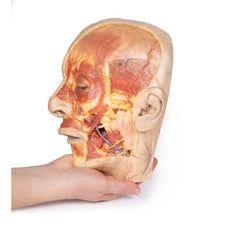

The deep level of dissection has exposed parts of the infratemporal fossa

(through partial removal of the mandibular ramus and corpus) and dissection

of retromandibular tissues. At the inferior margin of the dissection window,

the cut edge of the retromandibular vein lies adjacent to the submandibular

gland and the ascending path of the facial artery as it cross towards to angle

of the mouth. Just superior to the cut retromandibular vein is the posterior

belly of the digastric muscle, overlying a small exposure of the deeper

internal jugular vein.

Just posterior to the retained ascending ramus of the mandible are the

external carotid artery and the occipital artery (running in parallel prior

to passing posteriorly). Tracing the external carotid artery superiorly, the

posterior auricular artery, superficial temporal artery, and maxillary artery are

all visible. The maxillary artery passes deep to the lateral pterygoid muscle

and into the infratemporal fossa, reappearing superior to the lateral pterygoid

as it passes into the pterygomaxillary fissure. Along its course, it gives rise

to the posterior deep temporal artery, the inferior alveolar artery (which is

exposed in the dissected mandibular corpus), the anterior deep temporal

artery, and the posterior superior alveolar artery. Finally, the inferior alveolar

nerve can be seen coursing within the opened mandibular corpus, and the

lingual nerve resting on the medial pterygoid. The buccinator muscle is also

retained, with the distal part of the parotid duct preserved as it enters the

muscle towards the oral mucosa